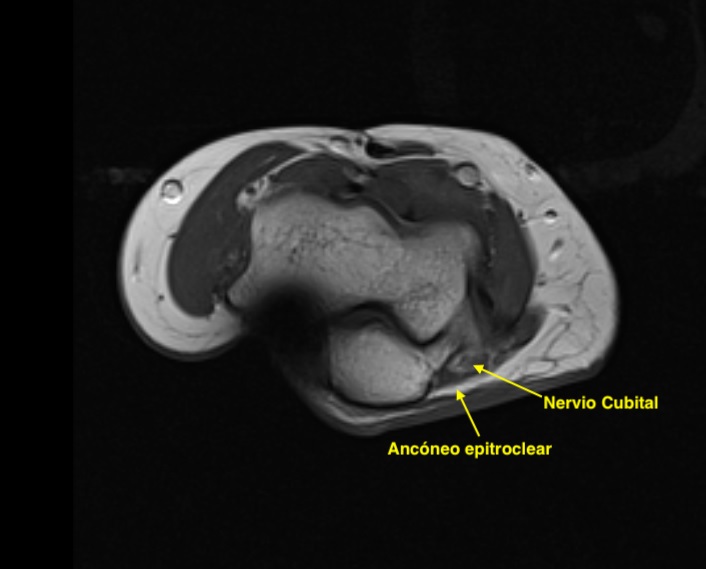

Ahora el ancóneo accesorio o epitroclear, recuerda, en la epitróclea:

Uno de los estudio más bonitos que he visto, espero que te haya gustado y a partir de ahora estés super atenta a esta localización y a este tipo de patologías…